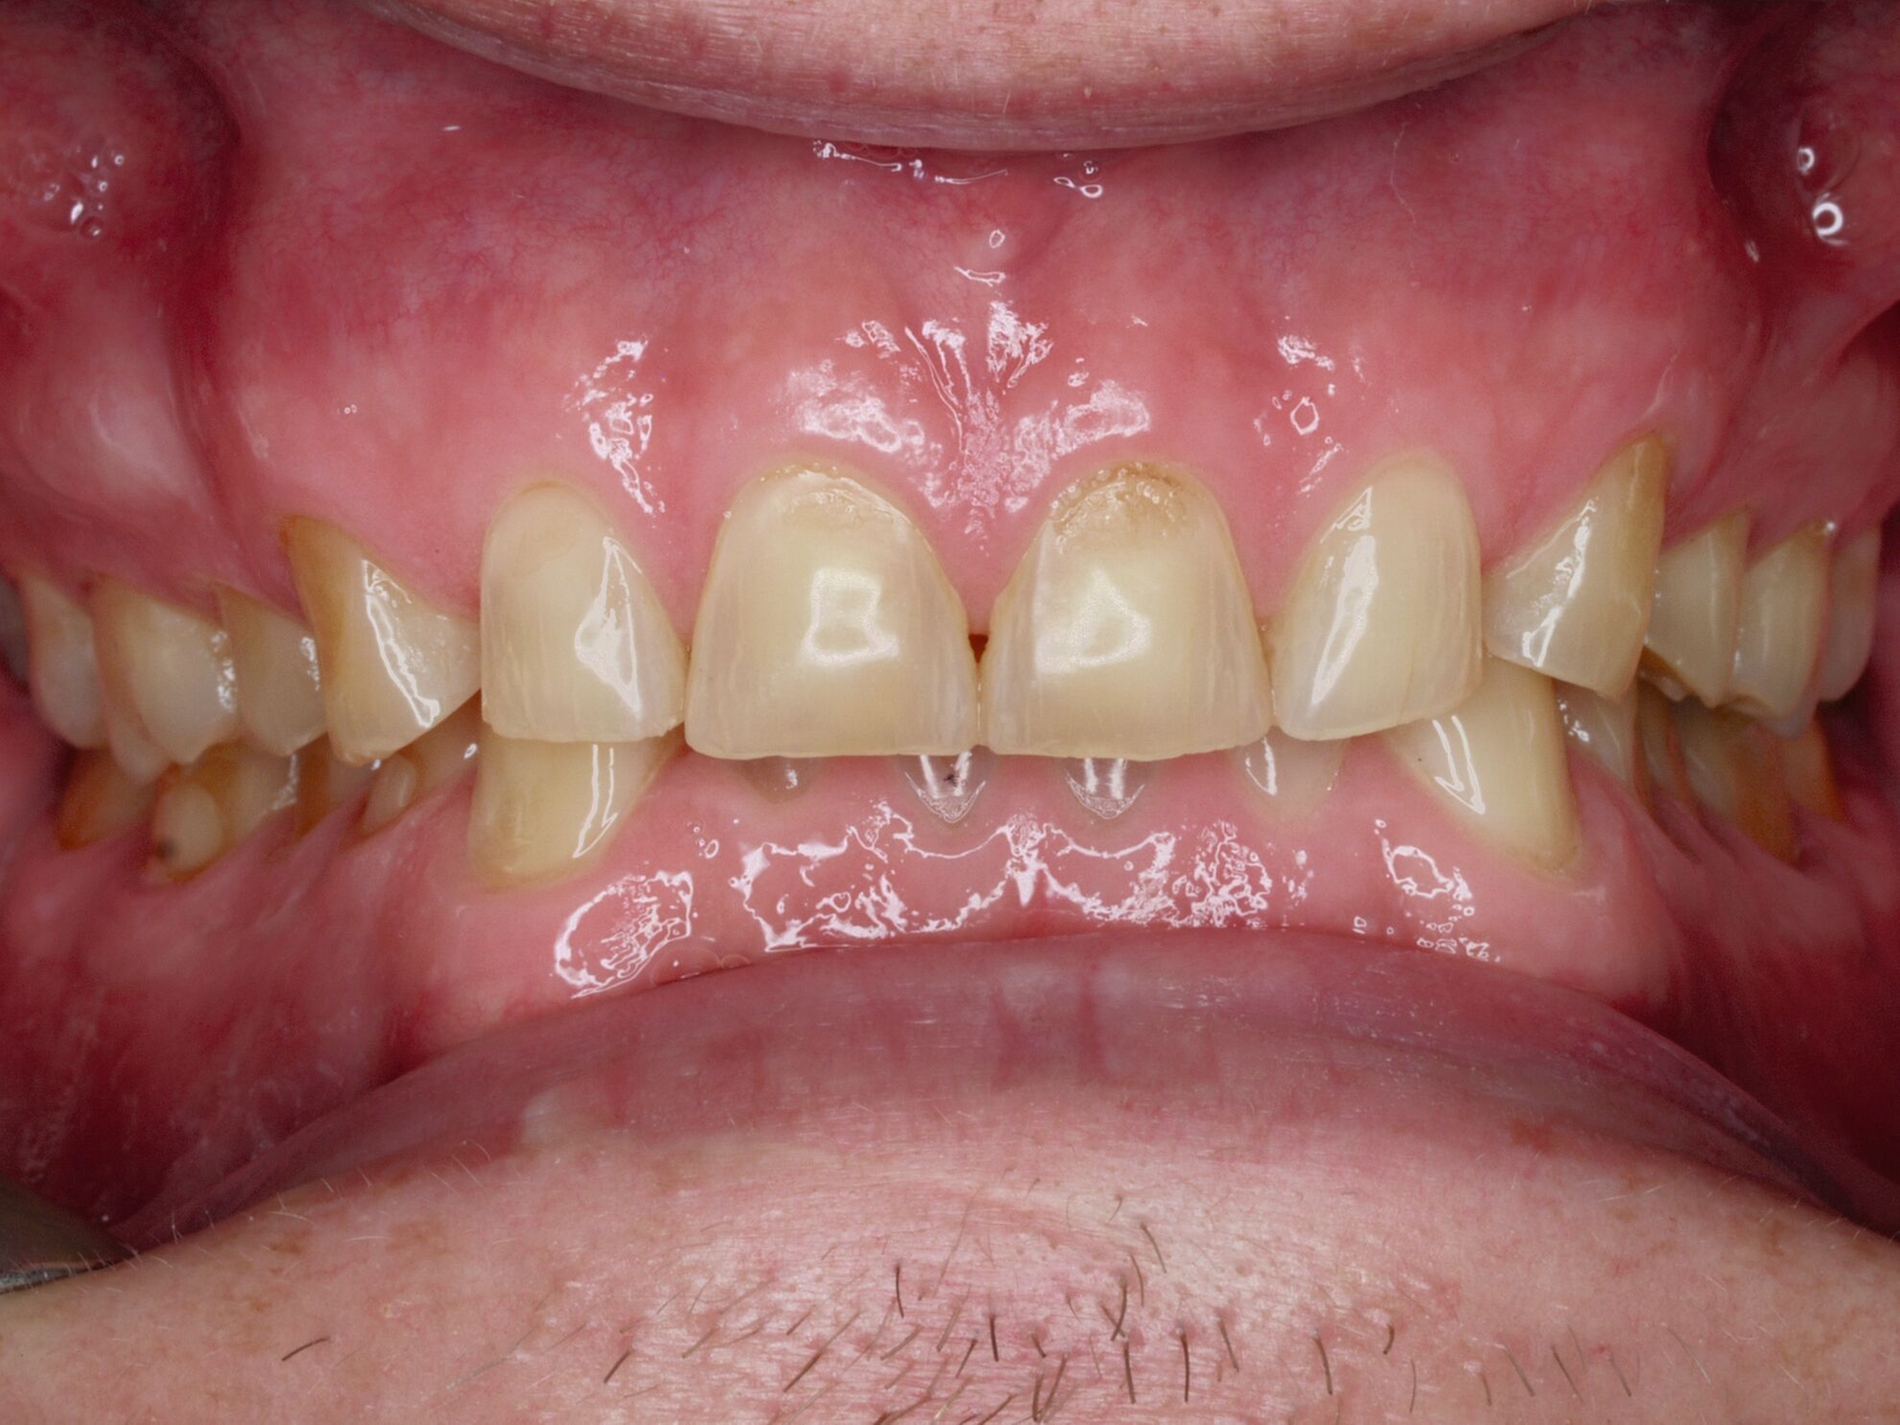

Das unter Beteiligung des Autors entwickelte Tooth Wear Evaluation System (TWES) 2.0 [Wetselaar et al., 2020] identifiziert per Screening Patienten mit erhöhten Verschleißwerten, vergleichbar mit dem PSI in der Parodontologie oder dem CMD-Kurzbefund. Bei auffälligen Werten folgt ein differenzierter Zahnverschleiß-Status einschließlich der Erfassung oraler und vestibulärer Substanzverluste [Wetselaar et al., 2016 sowie von Pathologie-Symptomen und einer strukturierten Diagnose [Tonetti und Sanz, 2019; Wetselaar, 2020]. Den Einsatz in der Praxis illustriert der in den Abbildungen beschriebene Patientenfall aus dem CMD-Centrum Hamburg-Eppendorf.

Im Beispiel ist daher die Diagnose ein generalisierter erheblicher und lokalisierter moderater pathologischer Zahnverschleiß überwiegend mechanischer und zudem chemischer Ursache. Die sich daraus ableitende Erkenntnis ist, dass in allen Sextanten Zähne freiliegende Dentinkerne aufweisen (generalisierter moderater Zahnverschleiß), dass darüber hinaus Zähne erheblich geschädigt und somit gefährdet sind, dass Merkmale eines pathologischen Geschehens bestehen – und dass als Ursache neben dem dominierenden Bruxismus ein Säureeinfluss hinzukommt.

Auch wenn Restaurationen nach Möglichkeit vermieden werden sollten, ist deren Verfügbarkeit für die Betroffenen individuell höchst wichtig, weil sie bestehende Schmerzen beseitigt, die verlorengegangene Kauleistung wiederherstellt und ästhetische und nicht zuletzt auch phonetische Einschränkungen aufhebt. Bei dem in den Abbildungen beschriebenen Fall korrelierte der erhebliche Zahnverschleiß mit der Lokalisation der Zahnschmerzen des Patienten. Direkte Restaurationen mit Kompositen hatten keinen Bestand. Die durchgeführte restaurative Behandlung hingegen hat Bestand, die Schmerzen waren danach umgehend verschwunden und sind seit zehn Jahren nicht wiedergekehrt.

Dabei führt die Verfügbarkeit hochfester Dentalkeramiken heute zu viel weniger invasiven Restaurationen als früher durchgängig übliche metallkeramische Kronen, und die Transluzenz der keramischen Werkstoffe ermöglicht zudem natürlichere Restaurationen. Der beschriebene Behandlungsfall zeigt, wie eine mehrstufige Zahnverschleiß-Diagnostik im Praxisalltag umgesetzt wird, mit initialem Zahnverschleiß-Screening und einer im Bedarfsfall erfolgenden erweiterten Diagnostik per Zahnverschleiß-Status.